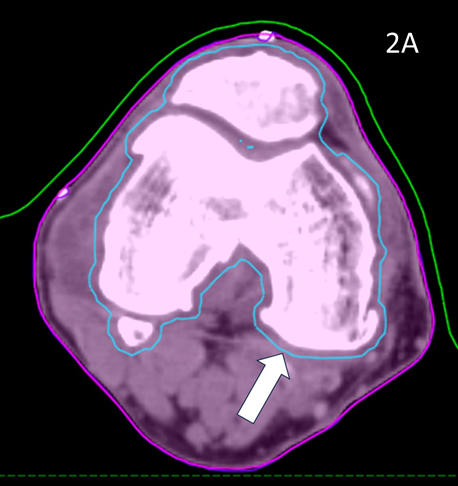

These volumes were then approved by the RO. The target volume was intended to be the joint including synovium with prescription to cover the PTV with 95% of the prescription dose. (Figure 2)

Figure 2 Contouring and dosimetry.

Figure 2A Axial planning CT slice through zero plane of knee in Figure 1A showing PTV (blue volume indicated by white arrow) as 2 mm expansion of CTV which was an auto contour of the bone.